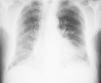

DiagnósticoPruebas de imagenEn la radiografía de tórax simple se puede apreciar un patrón intersticial o infiltrados reticulonodulares de distribución bibasal y periférica (subpleural) e hiperclaridad en los vértices con disminución de la trama vascular a ese nivel (fig. 1). Sin embargo, la radiografía de tórax puede inadvertir los hallazgos radiológicos de la CFPE, siendo la TCAR la exploración de referencia para confirmar el diagnóstico23,45. Las imágenes muestran la presencia de enfisema de predominio en lóbulos superiores, definido por una zona hipodensa bien delimitada sin pared, o con una pared muy fina y/o múltiples bullas, que coexiste con diversas manifestaciones radiológicas propias de las enfermedades difusas del pulmón, como lo son opacidades reticulares, bronquiectasias de tracción, áreas de engrosamiento septal, vidrio deslustrado y panal de abeja en lóbulos inferiores (fig. 2). Las lesiones enfisematosas corresponden a enfisema centrolobulillar y paraseptal (bullas subpleurales). El enfisema paraseptal se ha descrito hasta en una 90% de los casos, por lo que algunos autores sugieren que se trata de un rasgo característico de la CFPE1,23,46.

Radiografía de tórax de un paciente diagnosticado de combinación de fibrosis pulmonar y enfisema. Se observa afectación patrón intersticial bilateral, de predominio derecho con infiltrados reticulonodulares de distribución basal y subpleural y disminución de la densidad pulmonar en campos superiores, principalmente izquierdo.